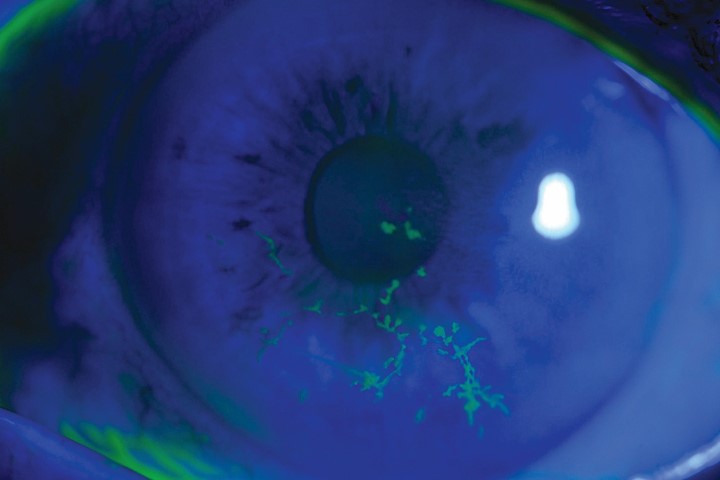

Review: This paper is the largest study looking at herpes zoster ophthalmicus (HZO) recurrence. The authors reviewed 869 patients with HZO treated at Auckland’s Greenlane Eye Clinic between 2006 and 2016 and found at least one recurrence of ocular inflammation in 200 subjects (23%) during a median follow up of 6.3 years. The median time from HZO onset to first recurrence was 3.5 months. Uveitis was the most common form of recurrence, followed by keratouveitis and keratitis. In subjects who required topical steroid treatment, the median time to recurrence was 1.4 months following steroid cessation.

Significant risk factors for recurrence include immunosuppression, higher presenting IOP, corneal involvement, and uveitis. Moderate vision loss (6/15 or worse) at final follow-up occurred in 19.6% of patients. There was a significant association between a greater number of recurrences and poorer final vision.

Comment: HZO is one of the most common acute eye conditions treated in eye emergency clinics. Recurrent ocular inflammation can lead to vision threatening complications such as neurotrophic keratopathy, glaucoma and optic neuropathy. This study highlights those patients at greater risk of recurrence so that measures can be taken to prevent poor visual outcomes. A longer taper of steroid may be required for higher-risk patients, such as immunosuppressed individuals and those with hypertensive kerato-uveitis. The general practice pattern at Greenlane Eye Clinic is a three-month gradual taper of topical steroids, along with monitoring for recurrence on steroid cessation.